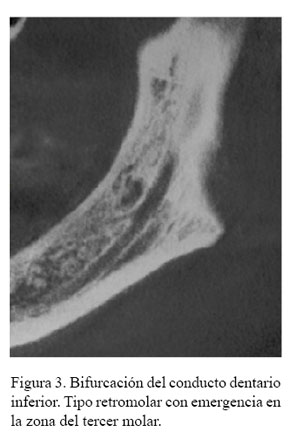

Tipo 1 (Canal retromolar): Consiste en una bifurcación del canal mandibular en la región de la rama mandibular, no alcanza piezas dentales, el conducto realiza una curva y alcanza la región retromolar (Figura 1 (A)).

En la tabla 3 se describe la distribución de la frecuencia del tipo de BCDI donde se encontraron 103 casos del tipo canal retromolar (Figura 2, figura 3 y figura 4); no se encontró ningún caso con el tipo de bifurcación canal bucal-lingual.